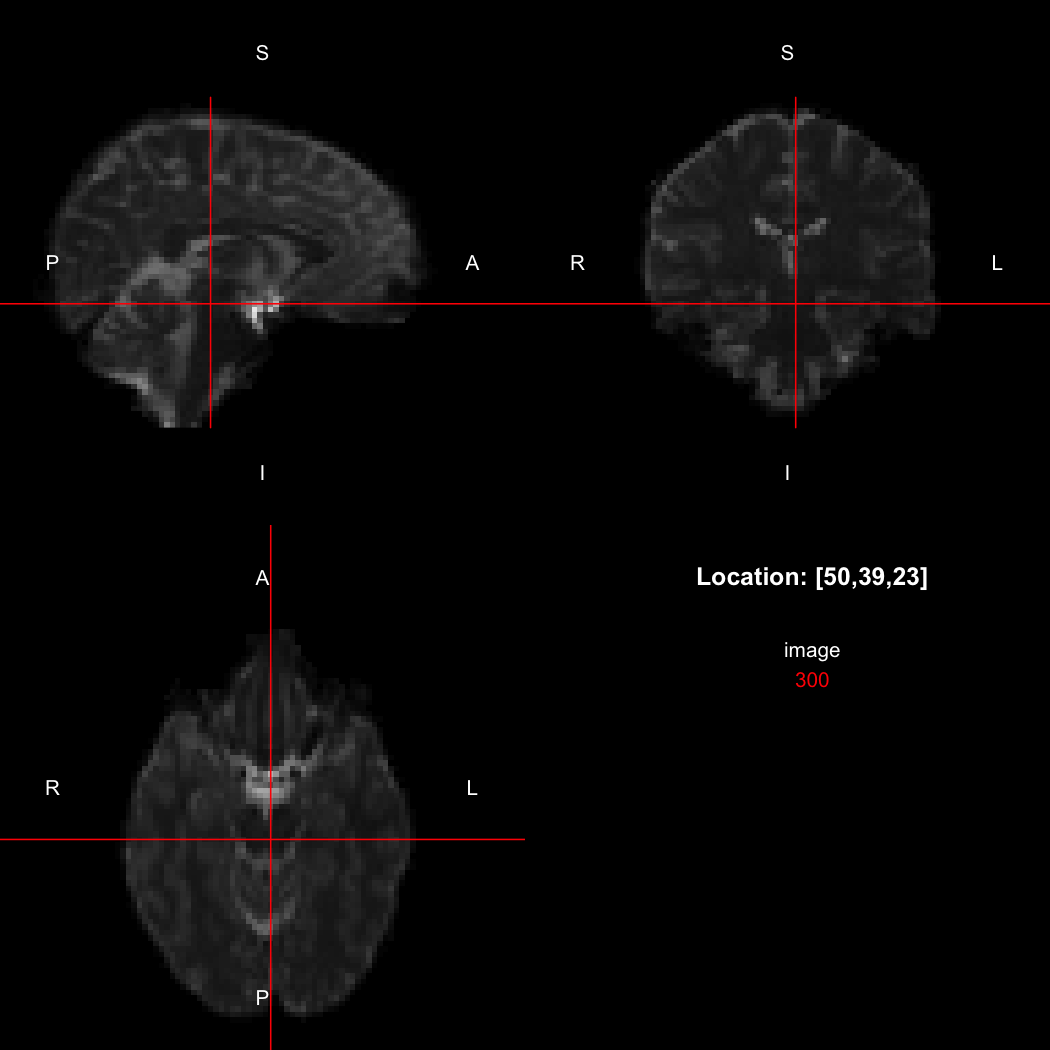

The package contains a basic image viewer, which can be used interactively or noninteractively to examine 2D or 3D images.

view(image)

plot of chunk unnamed-chunk-5

By default, the viewer shows labels indicating image orientation, crosshairs pinpointing the currently selected location, the numerical indices of the current location, and the value of the image at that location. Options allow each of these to be turned off, for the content of the bottom-right panel to be customised entirely, for the colour scale to be changed, and for additional images to be layered on top of the base image. See ?view for details.